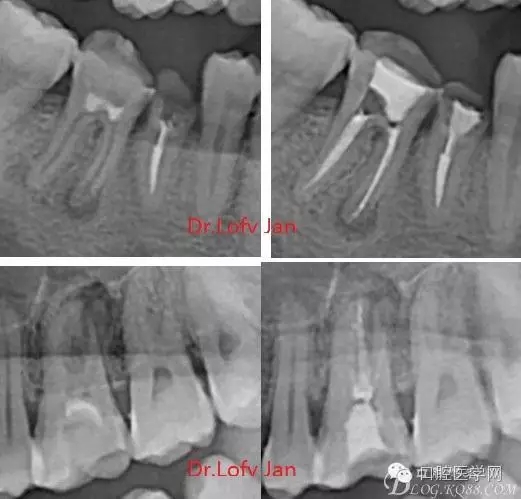

①有助于發(fā)現(xiàn)牙體和根尖周組織的異常改變,如牙折、牙內(nèi)吸收、髓腔鈣化及根尖囊腫;

②有助于確定牙根和根管的數(shù)目、位置、形態(tài)、方向和彎曲情況;

⑤評價根管充填的質(zhì)量以及療效。

病例分析:曲面斷層片在x線輔助診斷與檢查中目前大多數(shù)文獻(xiàn)和著作都建議只能作為初診拍片檢查手段,不能作為終末疾病的確診與手術(shù)療效的評價指標(biāo),臨床大部分中小型門診都因為設(shè)備不齊全導(dǎo)致信息偏差很大。